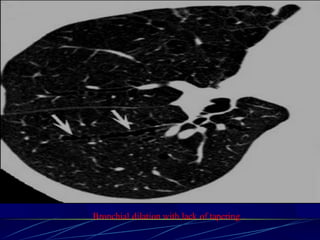

Bronchiectasis

Bronchiectasis is defined as localized bronchial

dilatation. (signet-ring sign)

bronchial wall thickening

lack of normal tapering with visibility of airways

in the peripheral lung

mucus retention in the broncial lumen

Signet-Ring Sign

A signet-ring sign represents an axial cut of a dilated bronchus

(ring) with its accompanying small artery (signet).

Tram Tracks

Bronchial dilation with lack of tapering .